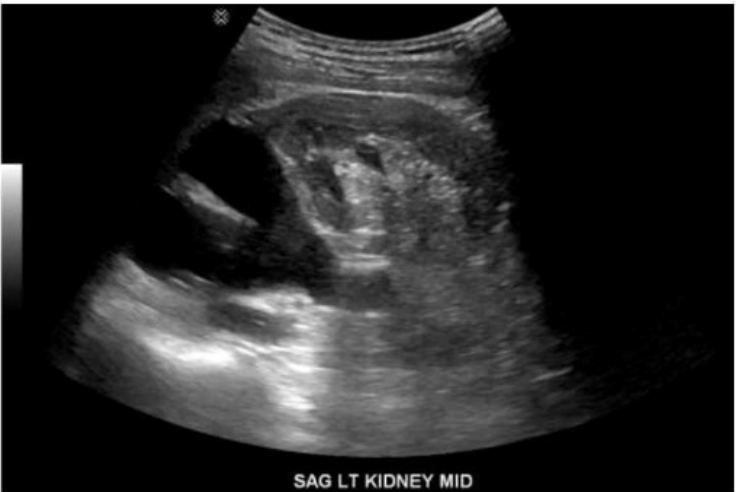

Which congenital anomaly is demonstrated in this image?

Answer : D

The ultrasound image labeled ''SAG LT KIDNEY MID'' demonstrates a left kidney with two separate, centrally located echogenic renal sinuses separated by intervening renal parenchyma. This appearance is classic for a duplicated collecting system.

A duplicated collecting system (also known as duplex kidney) is a congenital anomaly in which a single kidney contains two separate pelvicalyceal systems. It may be complete (with two ureters) or incomplete (partial duplication of ureters). This condition is one of the most common congenital anomalies of the urinary tract.

Sonographic Features of a Duplicated Collecting System:

Two separate central echogenic renal sinus regions seen within one kidney

Intervening parenchyma between the two sinuses

May show associated findings: hydroureteronephrosis (especially of upper pole moiety), ureterocele

Best visualized in sagittal plane

Differentiation from other options:

A . Horseshoe kidney: Shows fusion of the lower poles of the kidneys, typically located anterior to the aorta in the midline---not demonstrated here.

B . Crossed renal ectopia: One kidney is located on the opposite side of the body; this image shows a normally positioned kidney.

C . Prominent renal column (column of Bertin): May mimic a mass, but does not produce two separate sinuses as shown here.